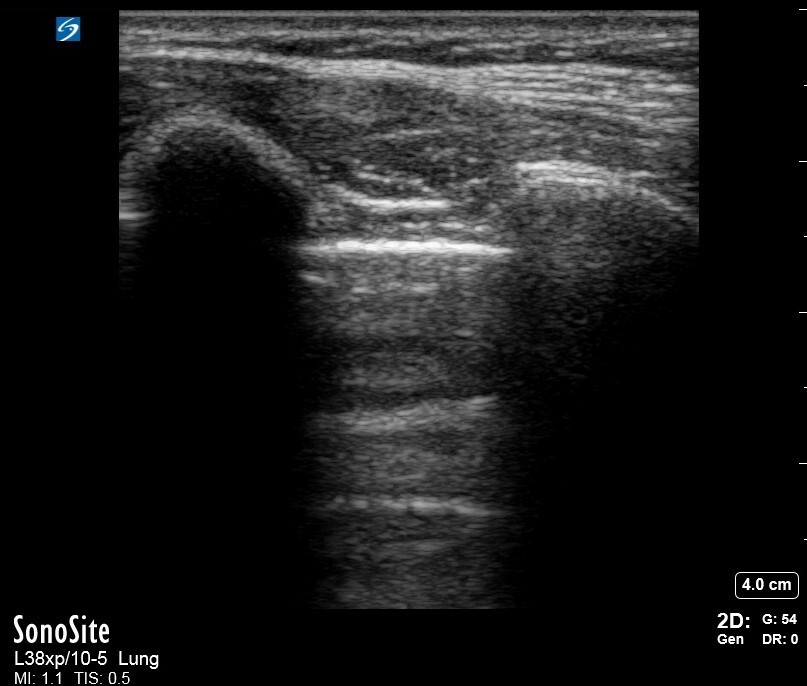

Pleura visceral y parietal pulmonar